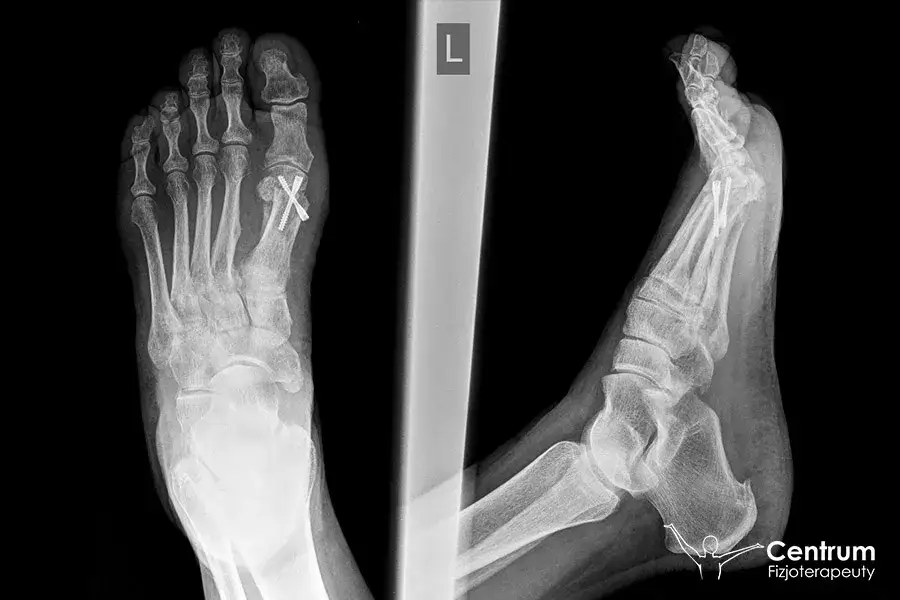

Skręcenie stawu skokowego: Rozpoznaj objawy i oceń powagę!

Skręcenie stawu skokowego: Poznaj objawy, stopnie urazu i pierwszą pomoc. Sprawdź, kiedy pilnie udać się do lekarza i jak odróżnić uraz.

Jaka maść na skręconą kostkę? Wybierz najlepszą bez recepty!

Jaka maść na skręconą kostkę? Sprawdź przewodnik po skutecznych preparatach bez recepty. Złagodź ból, obrzęk i przyspiesz leczenie. Dowiedz się, co wybrać!

Jak długo nie chodzić po skręceniu kostki? Czas i szybszy powrót

Ile trwa powrót do chodzenia po skręceniu kostki? Poznaj stopnie urazu, objawy i czas rekonwalescencji. Sprawdź, kiedy do lekarza i jak przyspieszyć leczenie!

Jak szybko wyleczyć skręconą kostkę? Plan działania i rehabilitacja

Skręcona kostka? Odkryj pilne metody na szybkie leczenie! Zminimalizuj ból, obrzęk i wróć do formy z protokołem POLICE i ćwiczeniami. Sprawdź nasz poradnik.